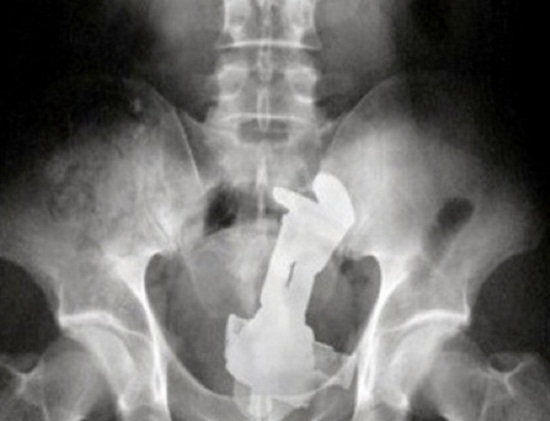

มาดูภาพเอกซเรย์ สารพัดสิ่งของที่เคยหลุดเข้าทวารหนัก

เผยภาพเอกซเรย์สุดอึ้ง สารพัดสิ่งที่เคยหลุดเข้าไปภายในทวารหนักผู้ป่วยทั่วโลก แปลกพิสดารกันจริง ๆ

การยัดสิ่งของต่าง ๆ เข้าไปในทวารหนักนั้น ไม่ว่าจะด้วยเหตุผลเพื่อหลบซ่อนการตรวจของเจ้าหน้าที่ทางการ หรือเป็นความผิดพลาดจากการแก้ขัดเมื่อเกิดอารมณ์ทางเพศก็ตาม สิ่งของที่หลุดเข้าไปนั้นล้วนแล้วแต่สร้างอันตรายให้กับอวัยวะภายในของผู้ป่วยได้หมด แต่ถึงจะเป็นอย่างนั้น เคสทางการแพทย์ว่าด้วยเรื่องของสิ่งแปลกปลอมที่หลุดเข้าไปในทวารหนักก็ยังมีให้เห็นอยู่เรื่อย ๆ ถมเถ แต่ละอย่างทำเอาอึ้ง ทึ่ง แบบไม่คิดว่ามันจะหลุดเข้าไปในทวารหนักได้จริง ๆ ดังเช่นตัวอย่างเคสที่เรานำมาฝากกันในวันนี้..

แว่นตาเก๋ ๆ